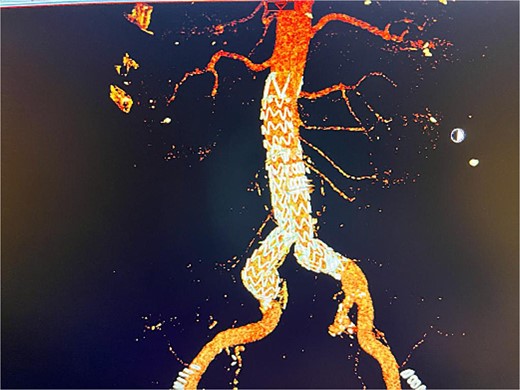

Given the anatomical complexity and the risk of injury to the hypogastric artery, we opted for EVAR, along with a flared limb extension to address the common iliac artery ectasia (Fig. 2). However, the patient experienced recurrent episodes of acute limb ischemia postoperatively, necessitating a thorough diagnostic and therapeutic approach.

Postoperative 3D reconstruction CTA image of the EVAR without any sign of endo leak.